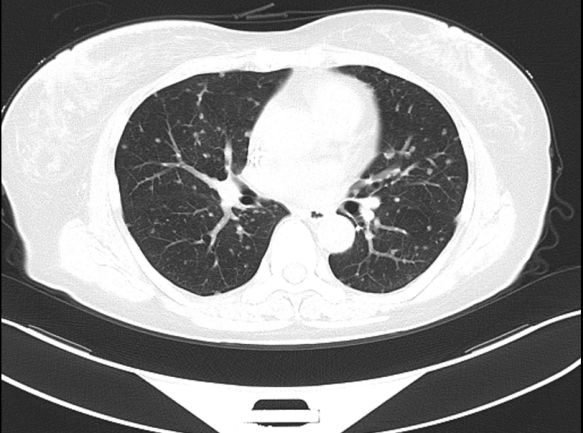

④三线治疗:曲妥珠单抗(汉曲优) 300mg Q3W+吡咯替尼 320mg QD+唑来膦酸4mg Q3M,并予以局部区域放疗。维持治疗至2022.03.31出现新发左肺转移灶及右侧小脑转移灶。行支气管镜检查,并取左肺下叶背段支气管开口见新生物活检,病理提示:(左肺结节)乳腺癌转移,Ki-67(20%,+),ER(-),PR(-),HER2(3+)。右侧小脑异常信号,1.2cm(图5),考虑转移。疗效评价PD,PFS 16个月。

图5. 2022.03左肺及右侧小脑影像图

⑤四线治疗:T-DM1 180mg Q3W;

两个疗程后评估:左肺下叶转移灶较前缩小,1.1cm;右侧小脑转移灶较前缩小,0.8cm(图6)。疗效评价 PR,继续维持该方案。

图6. 2022.05左肺及右侧小脑影像图